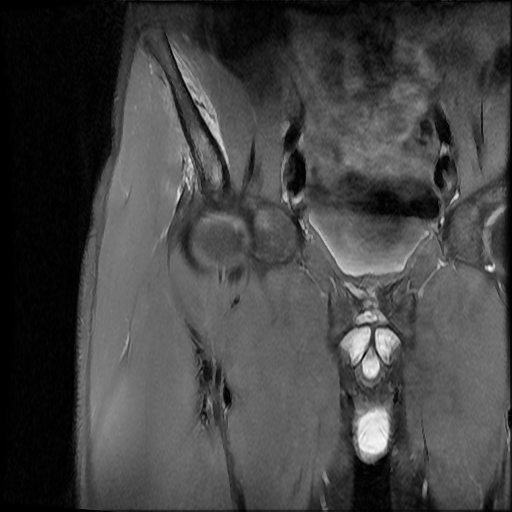

Popliteomeniscal Fascicles

Popliteomeniscal Fascicles: Anatomic Considerations Using MR Arthrography in Cadavers: AJR 2008; 190:442-448

Abnormal Superior Popliteomeniscal Fascicle and Posterior Pericapsular Edema: AJR 2001; 176:63-66